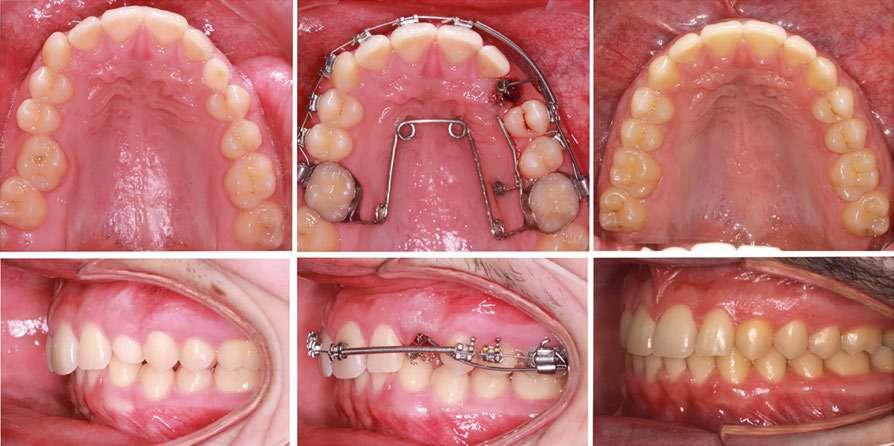

Caso clínico

A continuación se presenta el caso clínico de un varón de 30 años de edad sin antecedentes patológicos de interés, con antecedentes de tratamiento ortodóntico en la infancia, que durante una visita de mantenimiento y revisión periodontal expresó su preocupación por molestias al cepillado y recesiones a nivel de caninos superiores.

En la exploración clínica observamos recesiones gingivales múltiples en maxilar superior combinado con erosión de la encía y ligero desgaste cervical que borra la línea amelocementaria (Fig. 1). El sondaje periodontal en todos los dientes fue inferior o igual a 3 mm y no se detectaron puntos de sangrado al sondaje. Los dientes 1.3 y 2.3 mostraron ≤ 1 mm de encía queratinizada apical a la recesión. Cabe también destacar la rotación del incisivo lateral superior derecho (1.2). El principal factor etiológico de sospecha en este caso fue el cepillado agresivo.

Fase quirúrgica y restauradora

Después de un detallado análisis y valoración de las alternativas terapéuticas, se planificaron 2 procedimientos quirúrgicos mediante colgajos de avance coronal con acceso lateral y sin descargas para el tratamiento de las recesiones del maxilar superior (Fig. 2) (7-9).

A continuación procederemos a describir el paso a paso del tratamiento quirúrgico de las recesiones (Figs. 2 a 7). Ambos procedimientos quirúrgicos se realizaron bajo anestesia local y sedación consciente por vía endovenosa y con un tiempo de descanso para el paciente entre procedimientos de 1 mes y medio. En este caso, el eje de rotación fueron los caninos en ambos lados y todas las incisiones para-marginales oblicuas (líneas punteadas en rojo) se realizaron hacia estos dientes (Fig. 2).

Figura 1: Situación inicial. Obsérvese la recesión gingival profunda en 1.3 y 2.3, así como la erosión gingival y el borrado de la línea amelocementaria debido al cepillado agresivo.

caso clínicoCIRUGÍA BUCAL

los dientes 1.5, 2.4 y 2.5 para garantizar una correcta adaptación del

Figura 2. Planificación quirúrgica.

Figura 4. Diseño de las incisiones y del colgajo. Nótese la creación de una “falsa recesión” en

colgajo al finalizar el avance coronal.

Figura 3. Situación clínica el día de la intervención quirúrgica.

Figura 5. Colgajo elevado “Split-Full-Split” y fijación de los injertos de tejido conectivo con suturas 7/0 reabsorbibles (PGA).

Figura 7. Post-operatorio y excelente curación 7 días después de la cirugía.

Figura 6. Avance coronal sin tensión y sutura del colgajo mediante puntos “sling” con sutura 6/0 reabsorbible (PGA).

Cada incisión oblicua debía permitir el correcto movimiento lateral y coronal de la punta de la papila quirúrgica hacia su papila anatómica correspondiente. Las incisiones para-marginales oblicuas debían conectar la parte más apical de la recesión con un punto final ubicado en la base de la papila de los dientes vecinos. La altura de este punto final se midió desde la punta de la papila y corresponde a la altura de la recesión + 1 mm. Adicionalmente, para permitir llevar a cabo un colgajo sin descargas, conseguir el suficiente avance coronal a nivel de 2.3, así como una buena adaptación del colgajo en premolares, se realizaron “falsas recesiones” (10) a nivel de 2.4 y 2.5 (Fig. 4). Finalmente, y de acuerdo con los estudios de Stefanini y colaboradores (9), se planificó aplicar el injerto de tejido conectivo (ITC) de manera sitio-específica en los dientes 1.3 y 2.3 debido a la presencia de una banda de encía queratinizada apical a la recesión ≤ 1 mm (Fig. 2 y 5).

La elevación y preparación del colgajo incluyó un abordaje “split-full-split”. En primer lugar, se elevaron las papilas quirúrgicas a espesor parcial utilizando hojas de bisturí 15C. Luego, se realizó la elevación a espesor total en el tejido queratinizado apical a la recesión para exponer aproximadamente 3 mm de hueso apical a la dehiscencia ósea (se puede ver el área de exposición ósea apical a las recesiones) (Fig. 5).

Finalmente, se realizaron incisiones profundas y superficiales para disecar la porción apical del colgajo. La incisión profunda se hizo paralela al hueso en dirección apical para desprender las inserciones musculares del periostio, mientras que la incisión superficial se realizó paralela a la mucosa de revestimiento para liberar el epitelio del tejido conectivo y de las inserciones musculares.

Una vez que el colgajo bucal estuvo completamente elevado, se realizó la preparación radicular. Ésta incluyó:

 Raspado y alisado radicular: en este caso, solamente se raspó la superficie radicular con pérdida de inserción clínica.

 Acondicionamiento de la superficie radicular con EDTA al 24% durante 2 minutos.

 Y la aplicación de amelogeninas (Emdogain ® ).

Aunque se puede discutir la indicación de las amelogeninas en este caso concreto (recesiones amplias, alta convexidad radicular y/o raíces

prominentes), su uso tuvo como objetivo principal mejorar la cobertura radicular y facilitar la formación de una nueva inserción de tejido conectivo (8,11).

De acuerdo con la planificación quirúrgica, se tomaron injertos libres de epitelio y tejido conectivo del paladar (12). Colocando el injerto sobre un depresor lingual de madera y con la adecuada magnificación e iluminación, se des-epitelizó el injerto. Para obtener un grosor final homogéneo, de aproximadamente 0.8 - 1 mm de tejido conectivo, no solo se eliminó el epitelio, sino también el tejido graso del lado interno del injerto. Finalmente, se remodelaron los bordes del ITC para eliminar cualquier resto de epitelio y lograr una forma lo más regular posible. El injerto palatino se obtuvo del área entre el aspecto mesial del segundo premolar y la cara mesial del segundo molar. Inmediatamente después de obtener el injerto, la herida palatina se protegió con un agente hemostático (Surgicel ® ) y se suturó con suturas compresivas de PTFE 3/0 (Cytoplast ® ).

El uso de injertos de tejido conectivo des-epitelizados nos ofrece varias ventajas a nivel clínico (12), entre las cuales podemos destacar: una técnica de obtención del injerto más fácil, un tejido conectivo más denso, firme y estable, un menor riesgo de sangrado al no profundizar tanto como en otras técnicas y un mejor control del grosor del tejido conectivo.

Los ITCs se posicionaron y estabilizaron con suturas reabsorbibles simples de 7/0 (PGA - stoma®) (Fig. 5). Estas suturas iban desde aproximadamente 1 - 1.5 mm del borde del ITC hasta el periostio en la base de la papila anatómica. Los nudos se dejaron sobre el injerto para evitar un exceso de desplazamiento coronal. Por último, los colgajos se avanzaron coronalmente y se suturaron con suturas tipo “sling” de 6/0 para cubrir completamente los ITCs (Fig. 6).

La curación fue excelente y los puntos de sutura se retiraron a las 3 semanas post-operatorias (Fig. 7).

Seguimiento y evolución del caso

Se presentan fotografías clínicas de la evolución y seguimiento a 6 meses, 12 meses y a 5 años (Figs. 8-10). A pesar de una mínima recidiva de menos de 1 mm en la recesión del diente 2.1, es interesante y reconfortante observar la gran estabilidad clínica de los tejidos blandos, así como un color, textura y forma muy armónicos de toda la encía tratada. En gran parte también gracias a un excelente cepillado y mantenimiento periodontal.